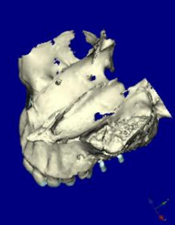

CTデータより3D画像を構築

左上に2本のインプラントを計画

上顎咬合面観